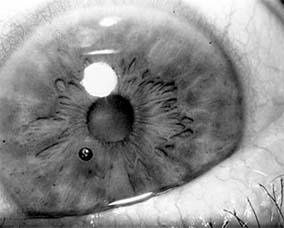

Figure 19-4

Figure 19-4: Choroidal ruptures. (Photo by Diane Beeston.)